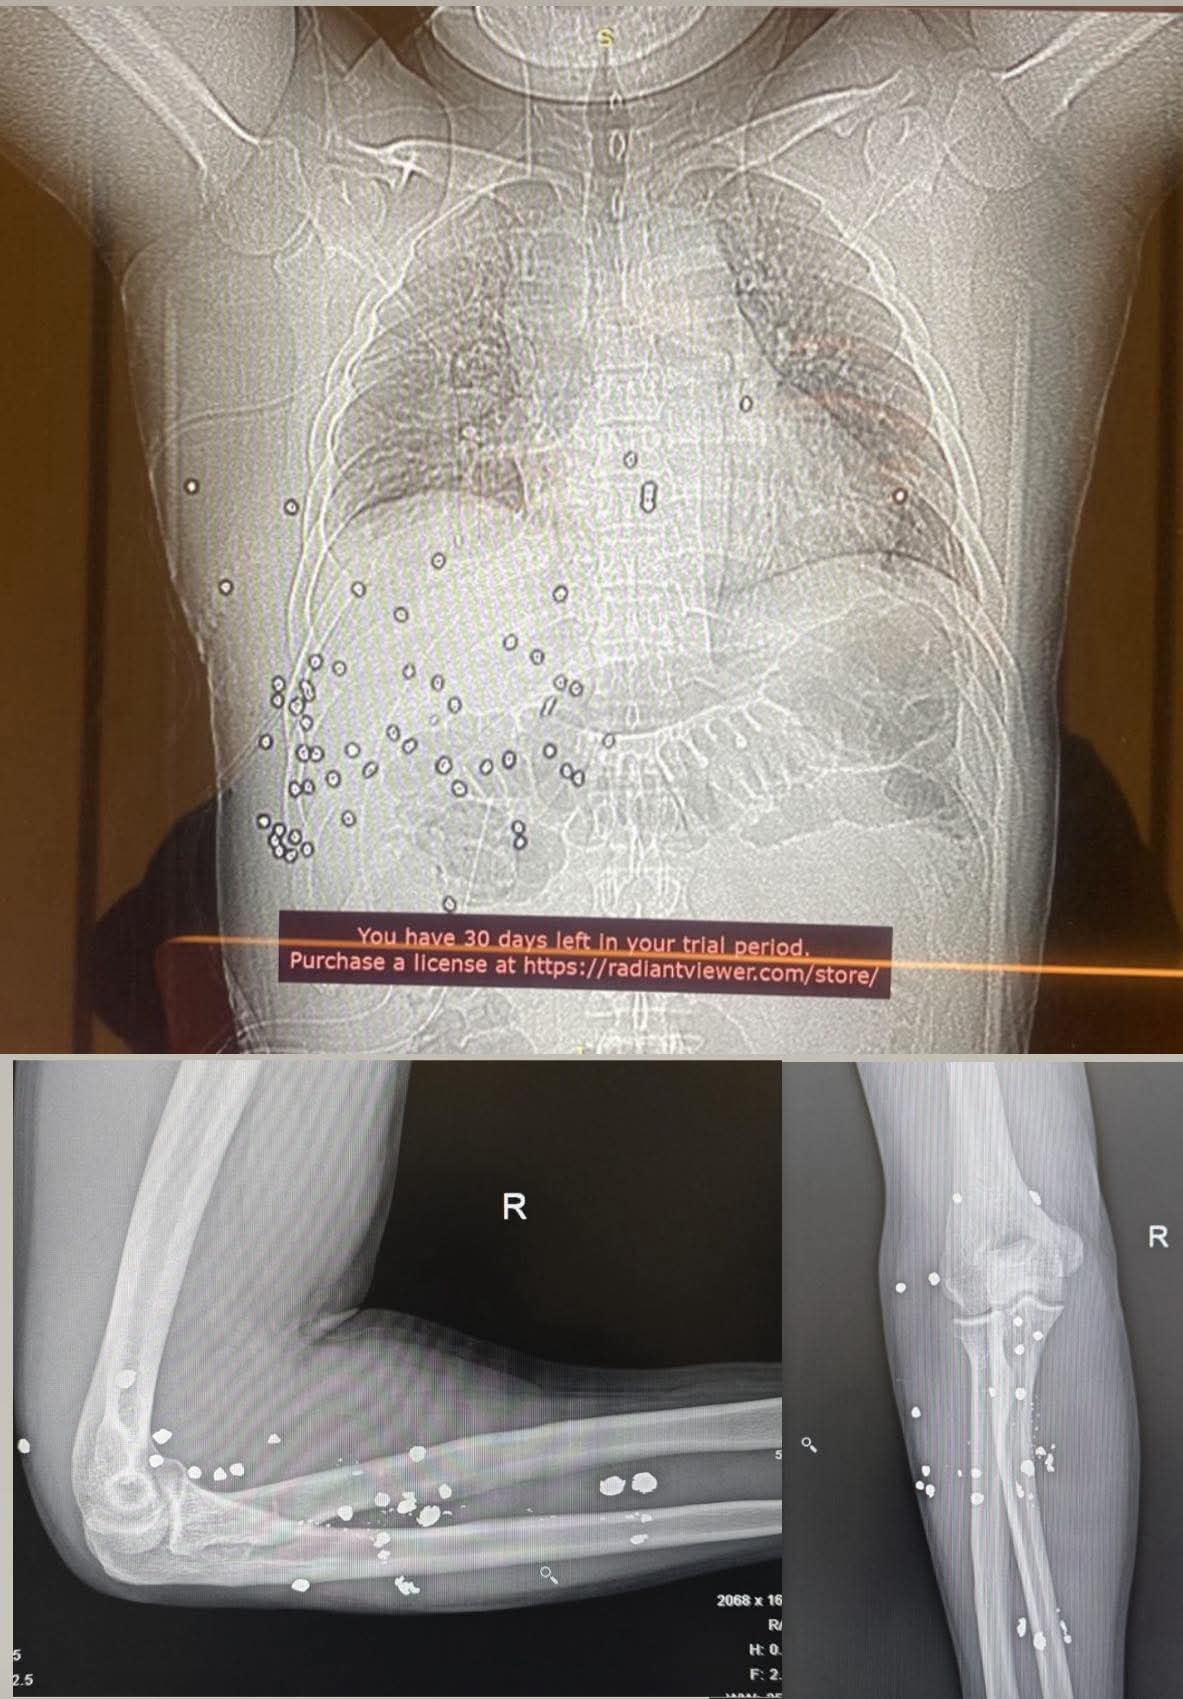

Руслан Берденов, заместитель акима Шымкента, который подвергся вооруженному нападению возле здания горадминистрации, показал свои рентгеновские снимки, передает Liter.kz.

Замакима приложил фото рентгена с оставшимися в его теле пулями.

"Свыше 60 дробей от охотничьего ружья до сих пор находятся в моeм теле. Это задокументированный факт", – написал Берденов.